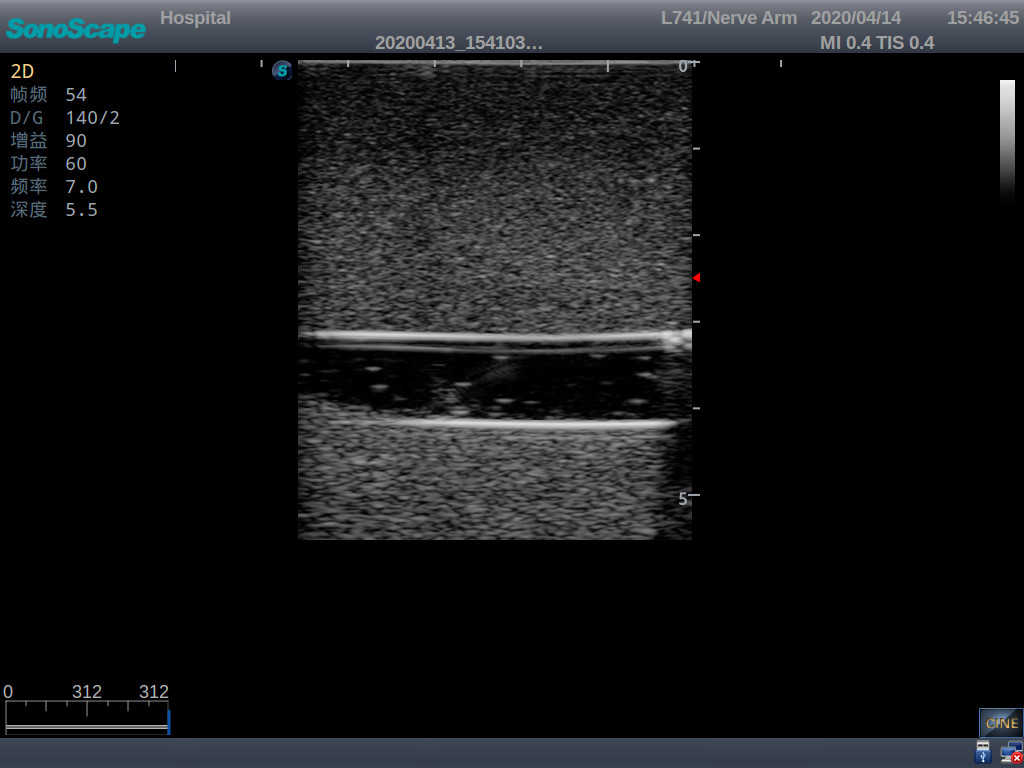

1)   Made of high molecular polymer ultrasound material, close to the real skin

2)   It can be used by real ultrasound machines

3)   Clear and real images of the tissues and organs (basilic vein and superior vena cava)

5)   Observe the guide wire marches